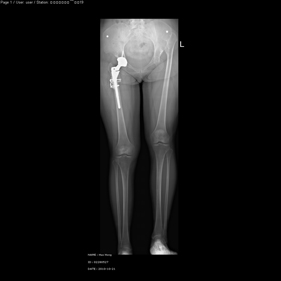

shortening osteotomy and total hip replacement for bilateral severe dysplasia of hip with high riding